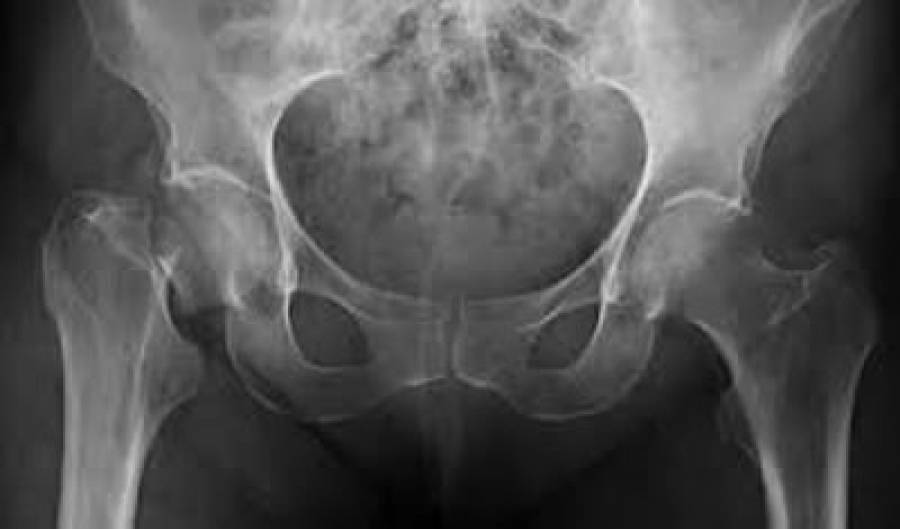

Caracterizada por una disminución de la masa ósea, lesiones de la microarquitectura del hueso, fragilidad excesiva del esqueleto y aumento del riesgo de fractura –aun a consecuencia de traumatismos menores en el contexto de las actividades cotidianas–, la osteoporosis se ha convertido en un importante problema de salud pública en China, conforme avanza el envejecimiento de la población.

En México, la prevalencia de osteoporosis en mujeres y hombres mayores de 50 años es de 17% y 9% en columna lumbar, respectivamente, y de 16% y 6% en cadera, respectivamente. Se estima que el riesgo de fractura de cadera a lo largo de la vida es de 8.5% en mujeres y 3.8% en hombres.3